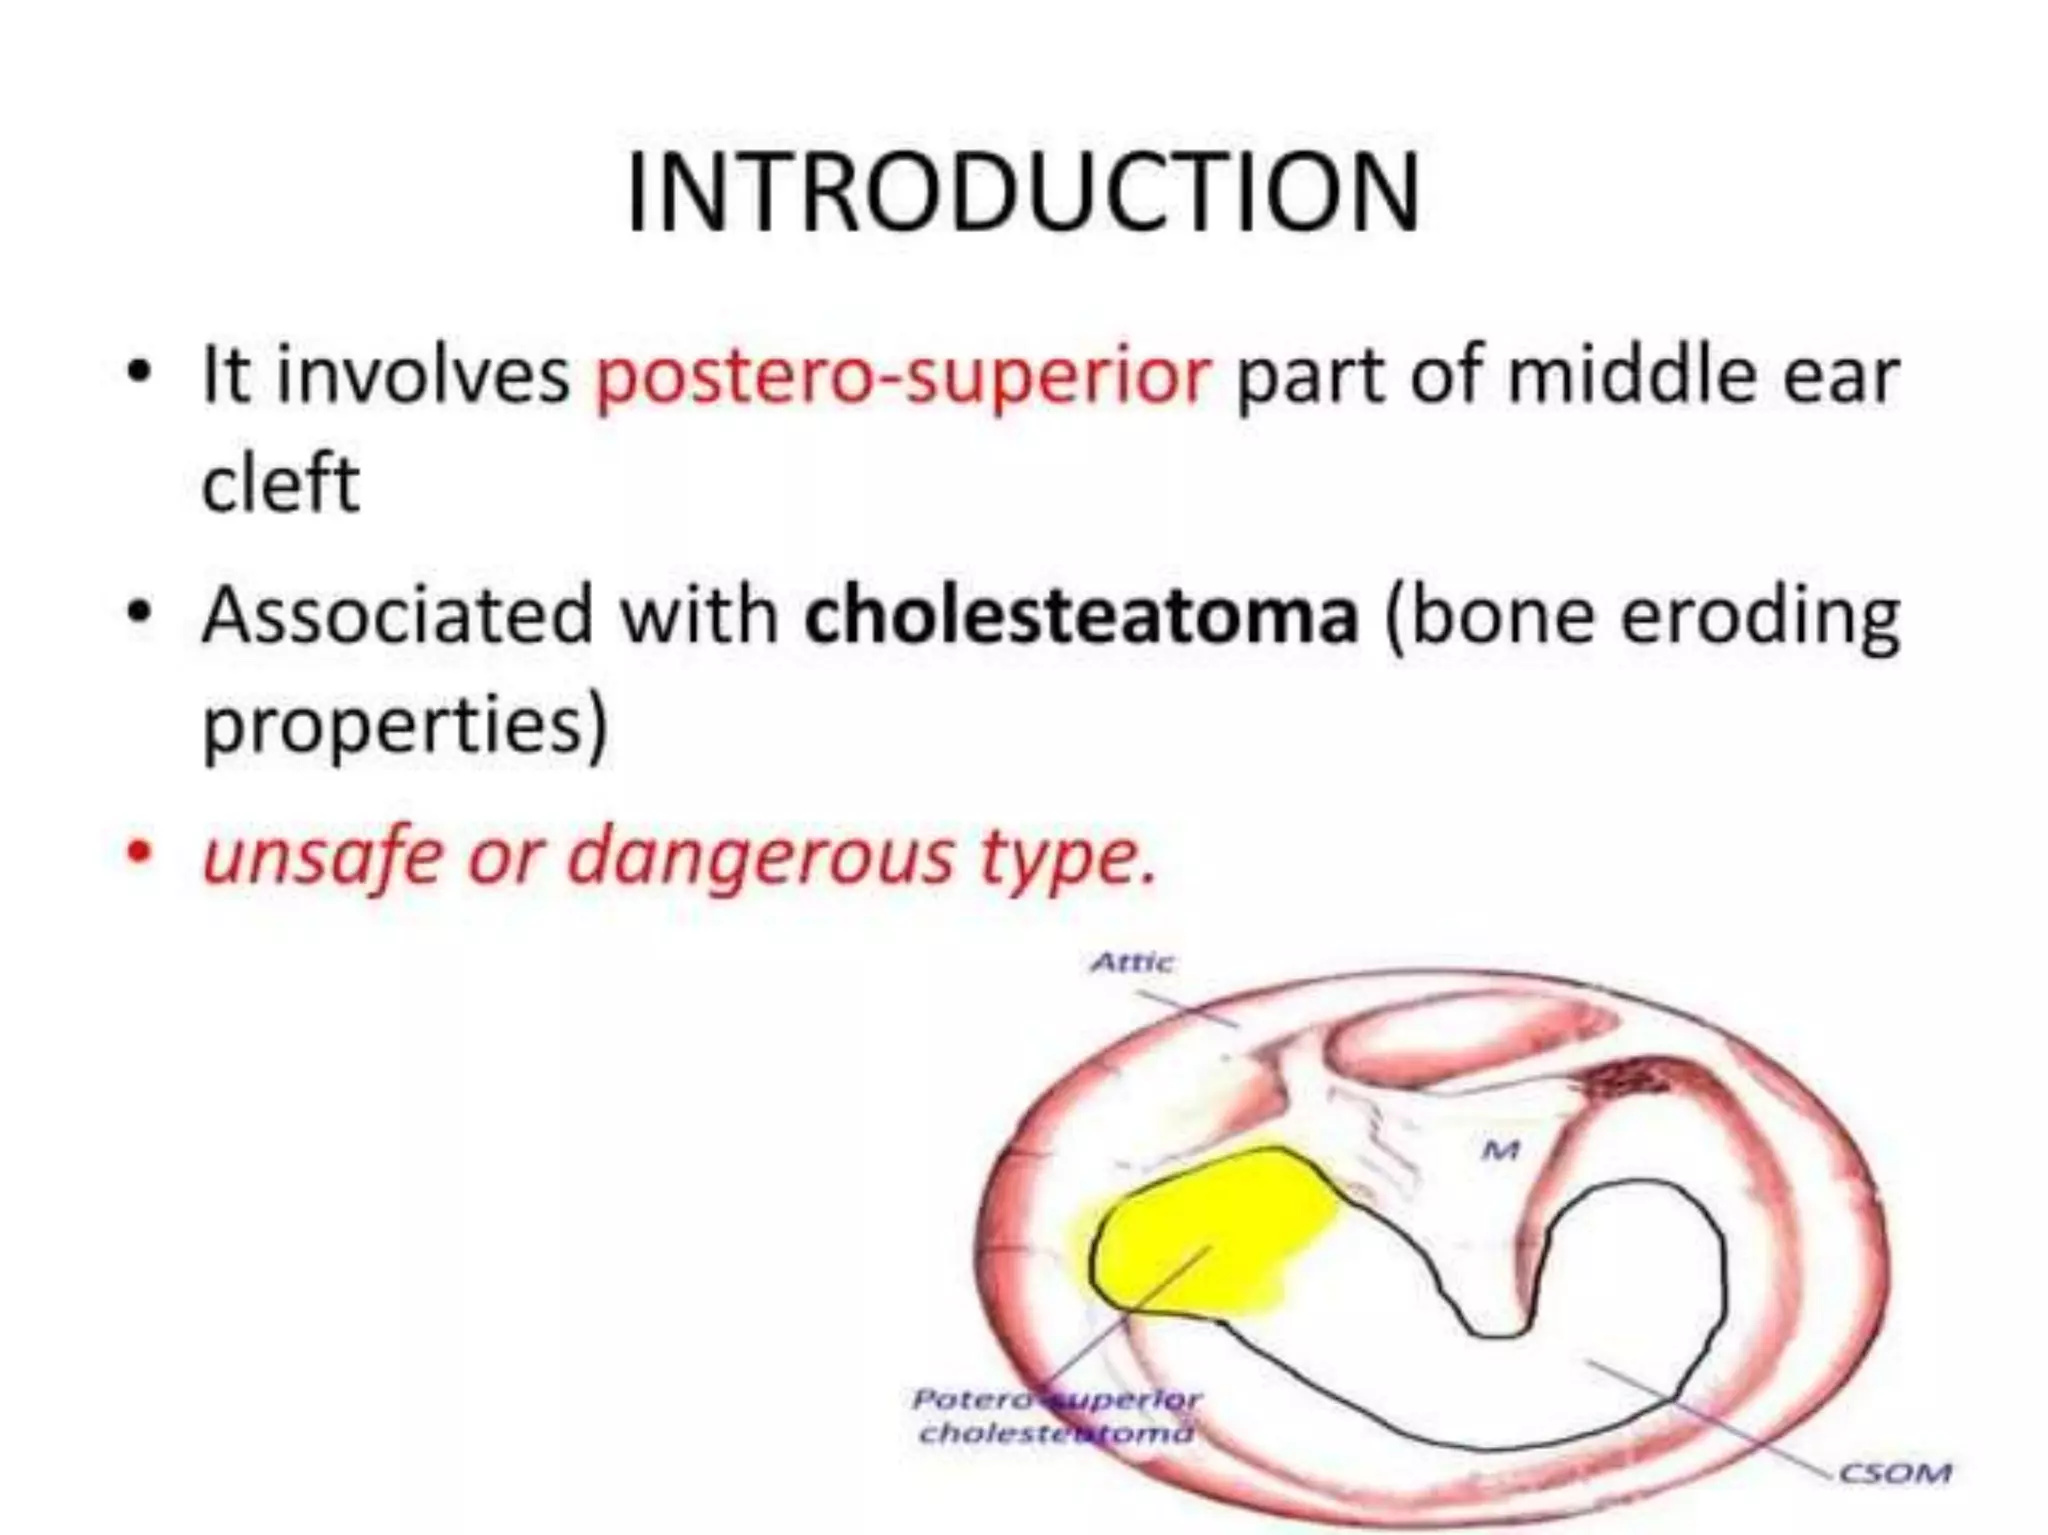

Chronic otitis media is a chronic inflammation of the middle ear and mastoid cavity that presents with recurrent ear discharge through a perforated eardrum. It has several subtypes depending on the state of the eardrum perforation and epithelium. It can be caused by prior acute otitis media, genetics, environment, eustachian tube issues, gastroesophageal reflux disease, craniofacial abnormalities, or immune deficiency.